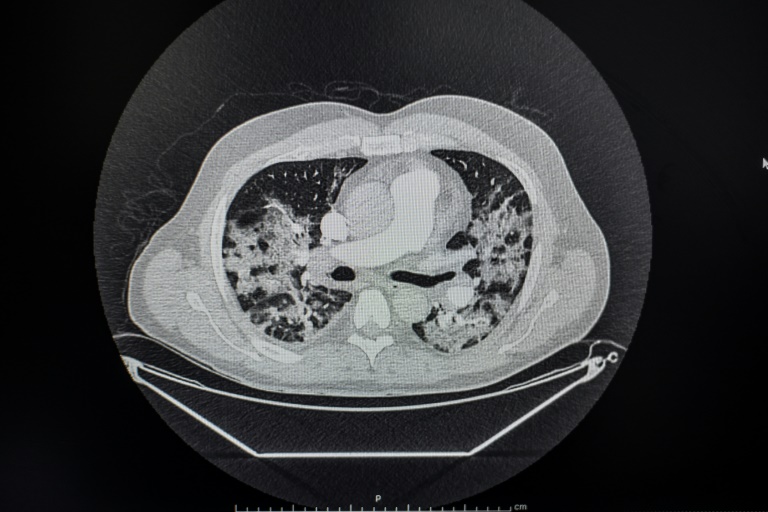

Transporté par le Samu à l'hôpital Cochin, il passe un scanner qui témoigne de lésions pulmonaires, le test nasal PCR confirme qu'il est positif au Covid-19: après une nuit aux urgences, le médecin est transféré en pneumologie et installé sous oxygène, avec un traitement antibiotique d'azythromycine.

Le 28 mars, la fièvre restant élevée, les médecins suspectent une embolie pulmonaire et prescrivent un angioscanner - accompagné d'une injection de produit révélateur dans les vaisseaux - qui écarte cette inquiétude. La fièvre finit par tomber. "Après 13 jours sous oxygène, le sevrage se passe bien, je peux partir". C'est le 4 avril.